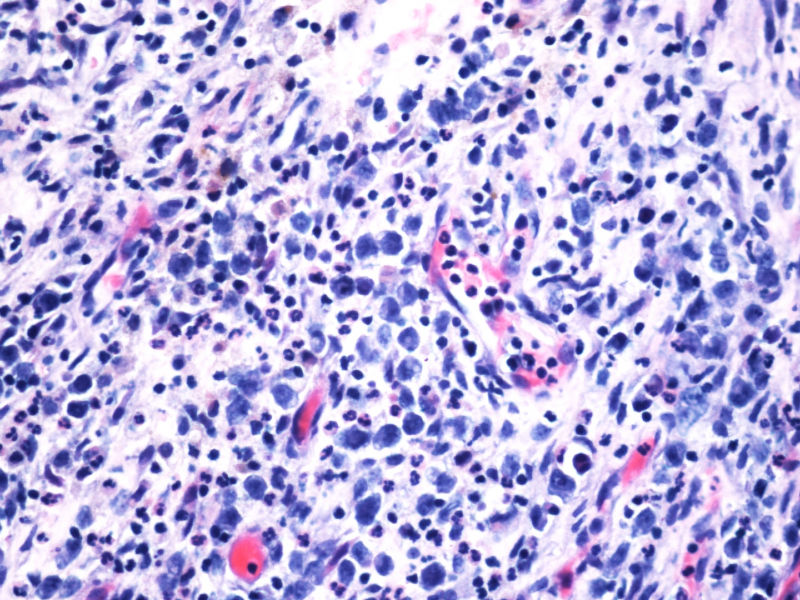

本例患者未查见淋巴结肿大,无肝脾肿大。其余标记物:大细胞显示CD2,CD3,CD4,CD8,CD5,EMA,TIA-1,GranB, oct, Bob1, EBER均阴性。

阳性的有CD30,CD15,CD43,ALK,perforin。

本例是大细胞病变;本例出现了“裸”免疫表型,这可在ALCL中出现;本例perforin阳性,支持是细胞毒性的大细胞淋巴瘤;大细胞同时表达CD30/CD15/ALK/细胞毒标志物,据目前文献报道,只有ALCL能解释;EBER阴性;临床影像学提示为溶骨性病变。。。

的确如此,CD43不仅表达于多量T细胞淋巴瘤,还可以表达于一些B细胞淋巴瘤,如套细胞淋巴瘤、小淋巴细胞淋巴瘤/白血病、粒细胞肉瘤等等,甚至还可以表达于一些非肿瘤细胞。本例CD2,CD3,CD4,CD8,CD5,CD7均阴性,在这样的大细胞病变形态基础上,此时做CD43和细胞毒标记物只是寻找诊断ALCL的佐证,后来果然CD43和部分细胞毒标志物是阳性,对于“裸”免疫表型的ALCL,这一诊断思路也是WHO和许多文献推荐的,日常工作中也是我们也常常是这样做的。如果病变是在淋巴结内,HE是大细胞病变,且出现上述免疫表型,我想应该有许多病理医生就诊断了ALCL了。只是本例部位等临床特征特殊,诊断需要慎之又慎,但最后ALK-1也显示大细胞阳性,就增加了诊断的信心。